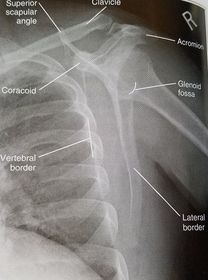

| AP Shoulder internal rotation | the MCP is tilted posteriorly as marked by the superior scapular angle is inferior to the clavicle |

| AP Shoulder | patient is rotated towards the unaffected shoulder: decreased thoracic superimposition over the scapular body |

| AP Shoulder | patient is rotated towards affected side:increased thoracic superimposition over the scapular body |

| AP Shoulder Neutral | ANATOMY: proximal humerus, lateral 2/3 of clavicle, open shoulder joint CRITERIA: humeral epicondyles are 45 degrees to the IR neither tubercle should be seen on the humeral head POSITIONING: CR perpendicular @ 1'' inferior to coracoid process |

| AP Shoulder Internal Rotation | CRITERIA: lesser tubercle in profile medially POSITIONING: CR perpendicular @ 1'' inferior to coracoid process |

| AP Shoulder External Rotation | CRITERIA: greater tubercle in profile laterally POSITIONING: CR perpendicular @ 1'' inferior to coracoid process |